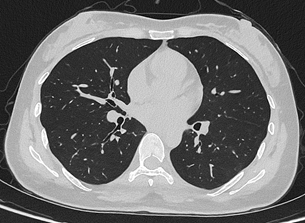

联影uCT Ultima扫描的0.2mm肺部超高清成像,扫描剂量低至0.1mSv

这背后,联影医疗研发团队进行了大量的技术攻坚。联影医疗CT事业部总裁杜岩峰介绍,“相比于传统CT,联影光子计数能谱CT在实现超高分辨率成像时,探测器的像素面积减小到原来的1/9,可以呈现更细微病变结构。同时,通过创新的校正算法和重建算法,解决了像素面积减小导致的信号强度降低的问题,抑制噪声并保证了图像质量。针对光子计数能谱CT大数据量处理这一痛点,联影医疗也进行了全面的技术创新,已实现全准直覆盖的超高分辨率与能谱同时成像,在心脏等需要大范围覆盖的检查中可做更深一步的探索。”